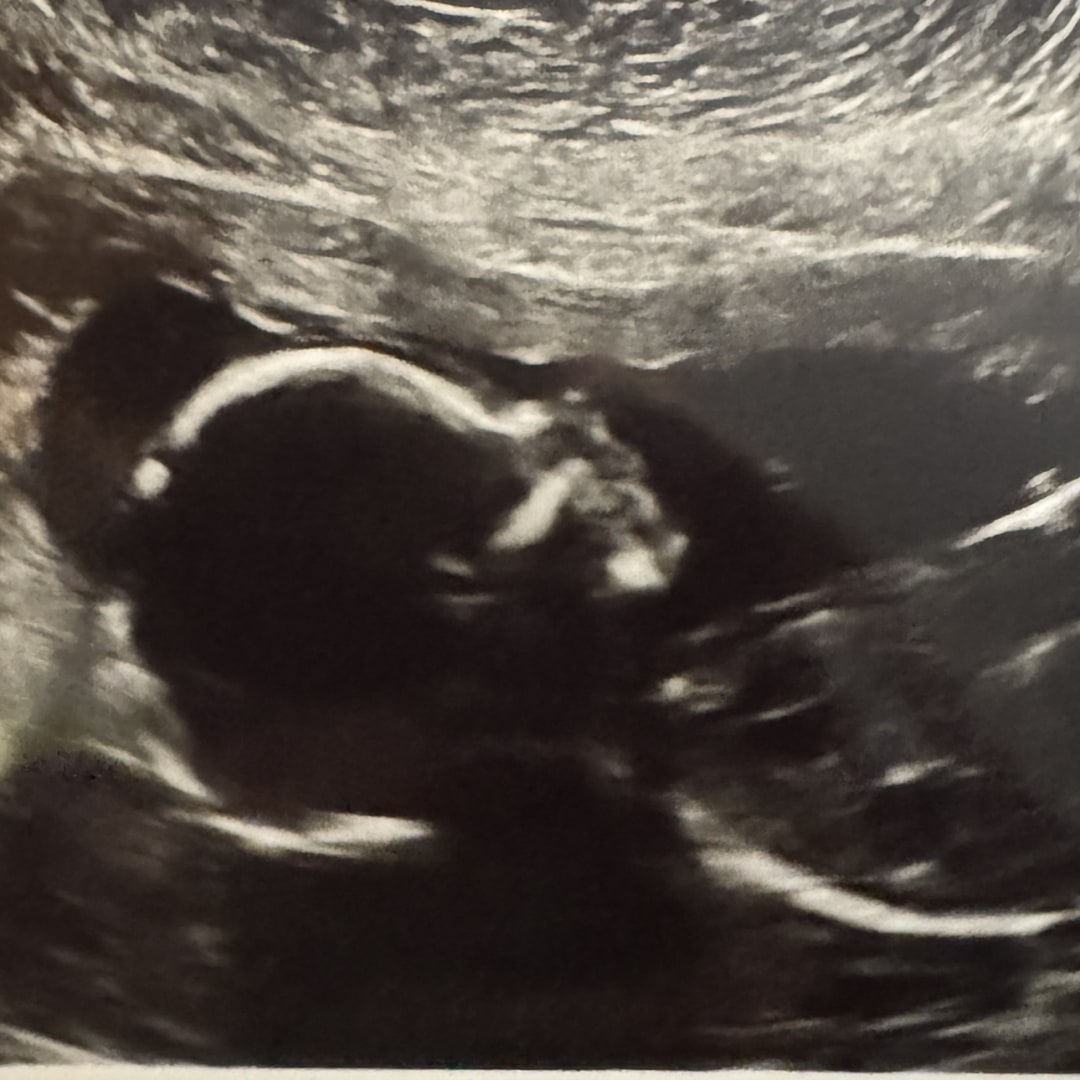

Hey y’all! So after nine years, just when we thought we had finally mastered things like sleeping through the night and owning furniture without mysterious stains, life surprised us with the most wonderful plot twist, a new baby is on the way.

More than anything, we’re grateful. This silly little goose is such a gift, and having friends and family who are excited to welcome her with us means the world. Your love, laughter, and support are truly what we cherish most, everything else is just a bonus.